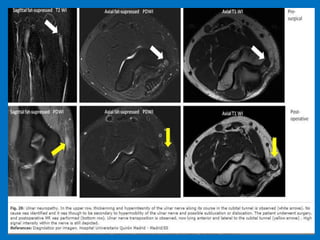

Cubital tunnel syndrome. Axial and sagittal proton density MR image shows ulnar nerve

(arrow) compressed against medial epicondyle (ME) by anconeus epitrochlearis (AE).